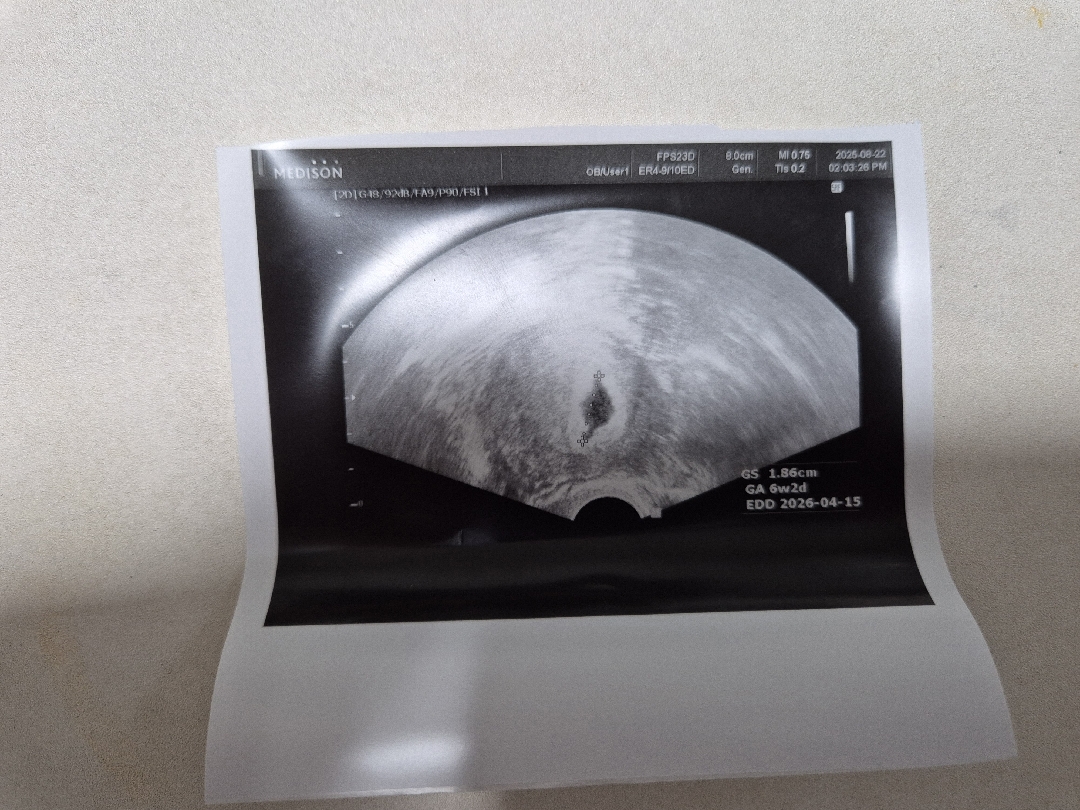

오늘 5주4일차인데 걱정되서 서브병원갔더니 6주 2일이라고 하시는데 아기집모양이 바람빠진풍선이라고 표현하셨는데 좋다,괜찮다는 얘기는 안해주시고 다음주에 원래병원가서 확인해보라고 하시네요....모양이 안좋은가요? 첫째도 유산한 경험이 있어서 너무 불안합니다